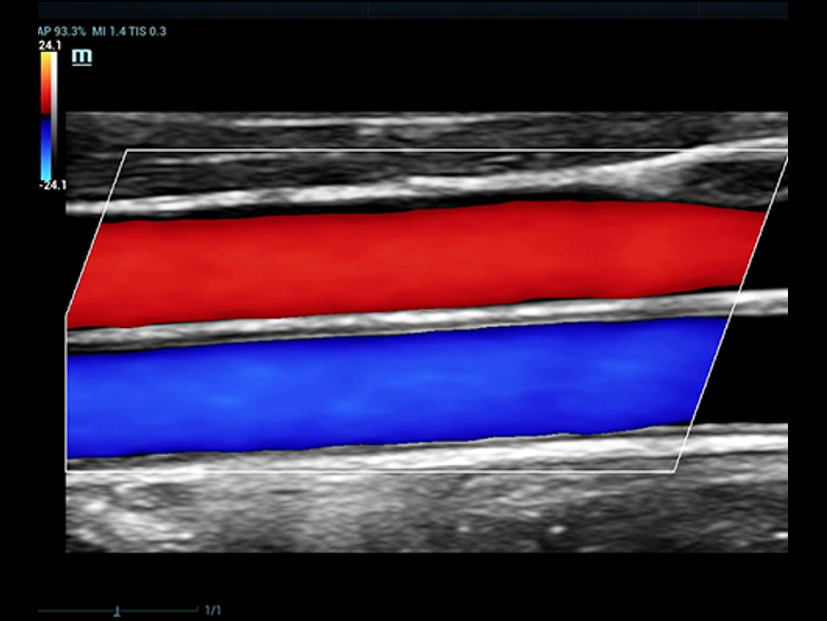

Oltre alla qualit├Ā delle immagini di livello eccellente, Resona 7 migliora anche le capacit├Ā di ricerca clinica il rivoluzionario V Flow per la valutazione emodinamica vascolare, e l'acquisizione piani pi├╣ intelligente dal set di dati 3D per la diagnosi del sistema nervoso centrale fetale. Combinando il pi├╣ intuitivo funzionamento multi-touch basato su gesti e tutte le caratteristiche cliniche essenziali, Resona 7 sta veramente portando nuove tendenze nellŌĆÖinnovazione dellŌĆÖecografia.